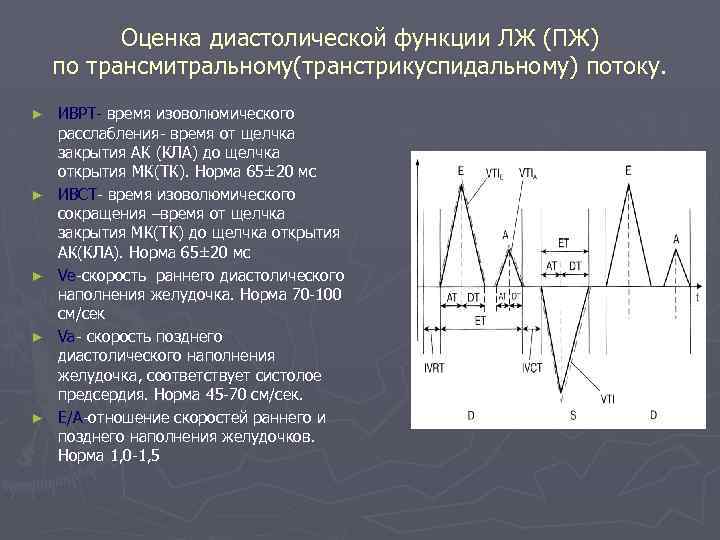

Оценка диастолической функции ЛЖ (ПЖ) по трансмитральному(транстрикуспидальному) потоку. ► ► ► ИВРТ- время изоволюмического расслабления- время от щелчка закрытия АК (КЛА) до щелчка открытия МК(ТК). Норма 65± 20 мс ИВСТ- время изоволюмического сокращения –время от щелчка закрытия МК(ТК) до щелчка открытия АК(КЛА). Норма 65± 20 мс Ve-скорость раннего диастолического наполнения желудочка. Норма 70 -100 см/сек Va- скорость позднего диастолического наполнения желудочка, соответствует систолое предсердия. Норма 45 -70 см/сек. Е/А-отношение скоростей раннего и позднего наполнения желудочков. Норма 1, 0 -1, 5